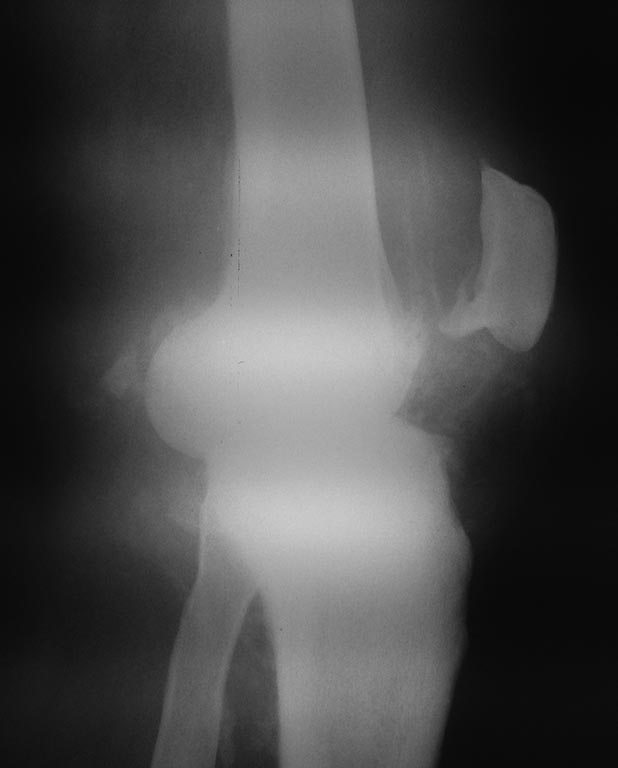

[Ortho] Постсифилитическая артропатия

Коллеги поделитесь опытом пожалуйста, в методах лечения сустава Шарко

правого коленного

сустава, заранее благодарен.